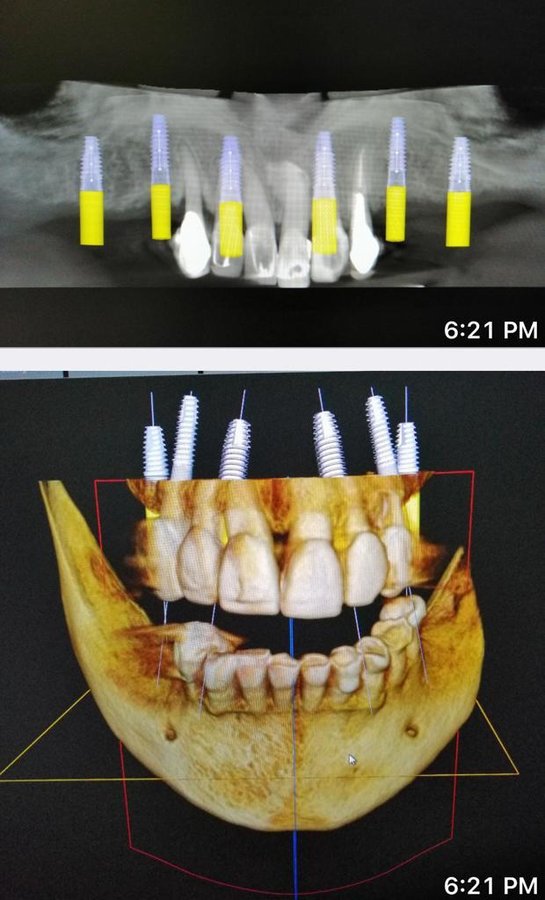

About Live Implants Nicaragua Virgil Mongalo DMD is a dental implant surgeon, past professor of implant surgeries at the University of Miami and the University of Florida has opened a surgical implant center in Managua. This is a state of the art facility consisting of equipped with Ct-scan, 3D Printer, zirconia milling machine, 8 surgical rooms, and USA sterilization controls. His team consists of implant surgeries professor accredited... (Show more)